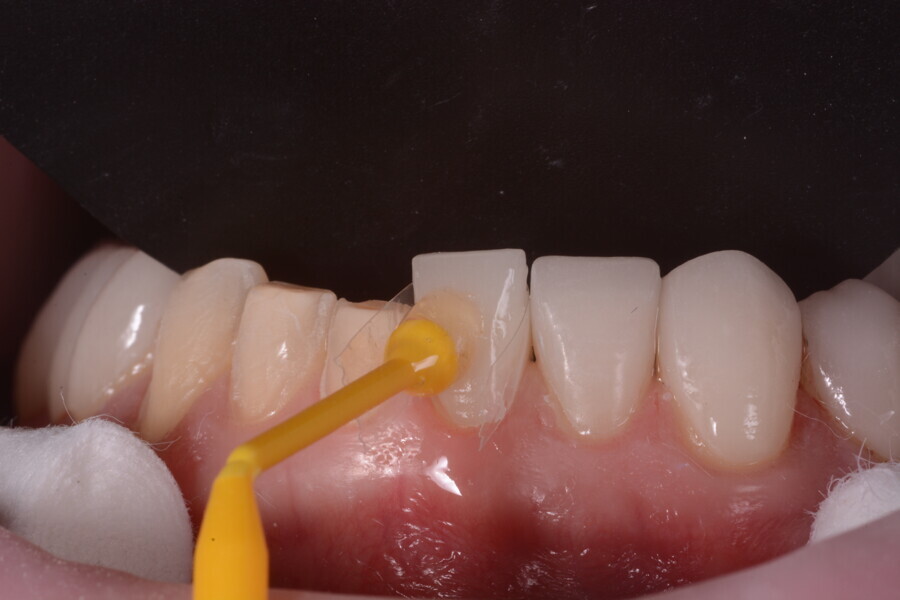

Fig. 11: The crowns (#11–13 and 21–23) and veneers (#14–17, 24–27, 31–37 and 41–47) were secured to the abutments using a light-cured resin adhesive (Futurabond U and Bifix QM).

Fig. 12: The crowns (#11–13 and 21–23) and veneers (#14–17, 24–27, 31–37 and 41–47) were secured to the abutments using a light-cured resin adhesive (Futurabond U and Bifix QM).